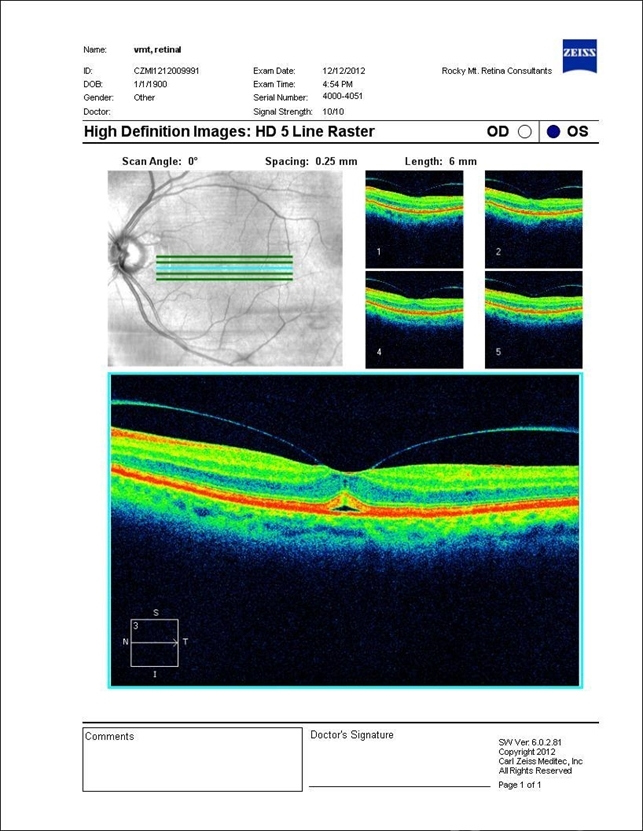

- vitreoretinal traction

- Optical coherence tomography system

- Vitreal Macular Traction.